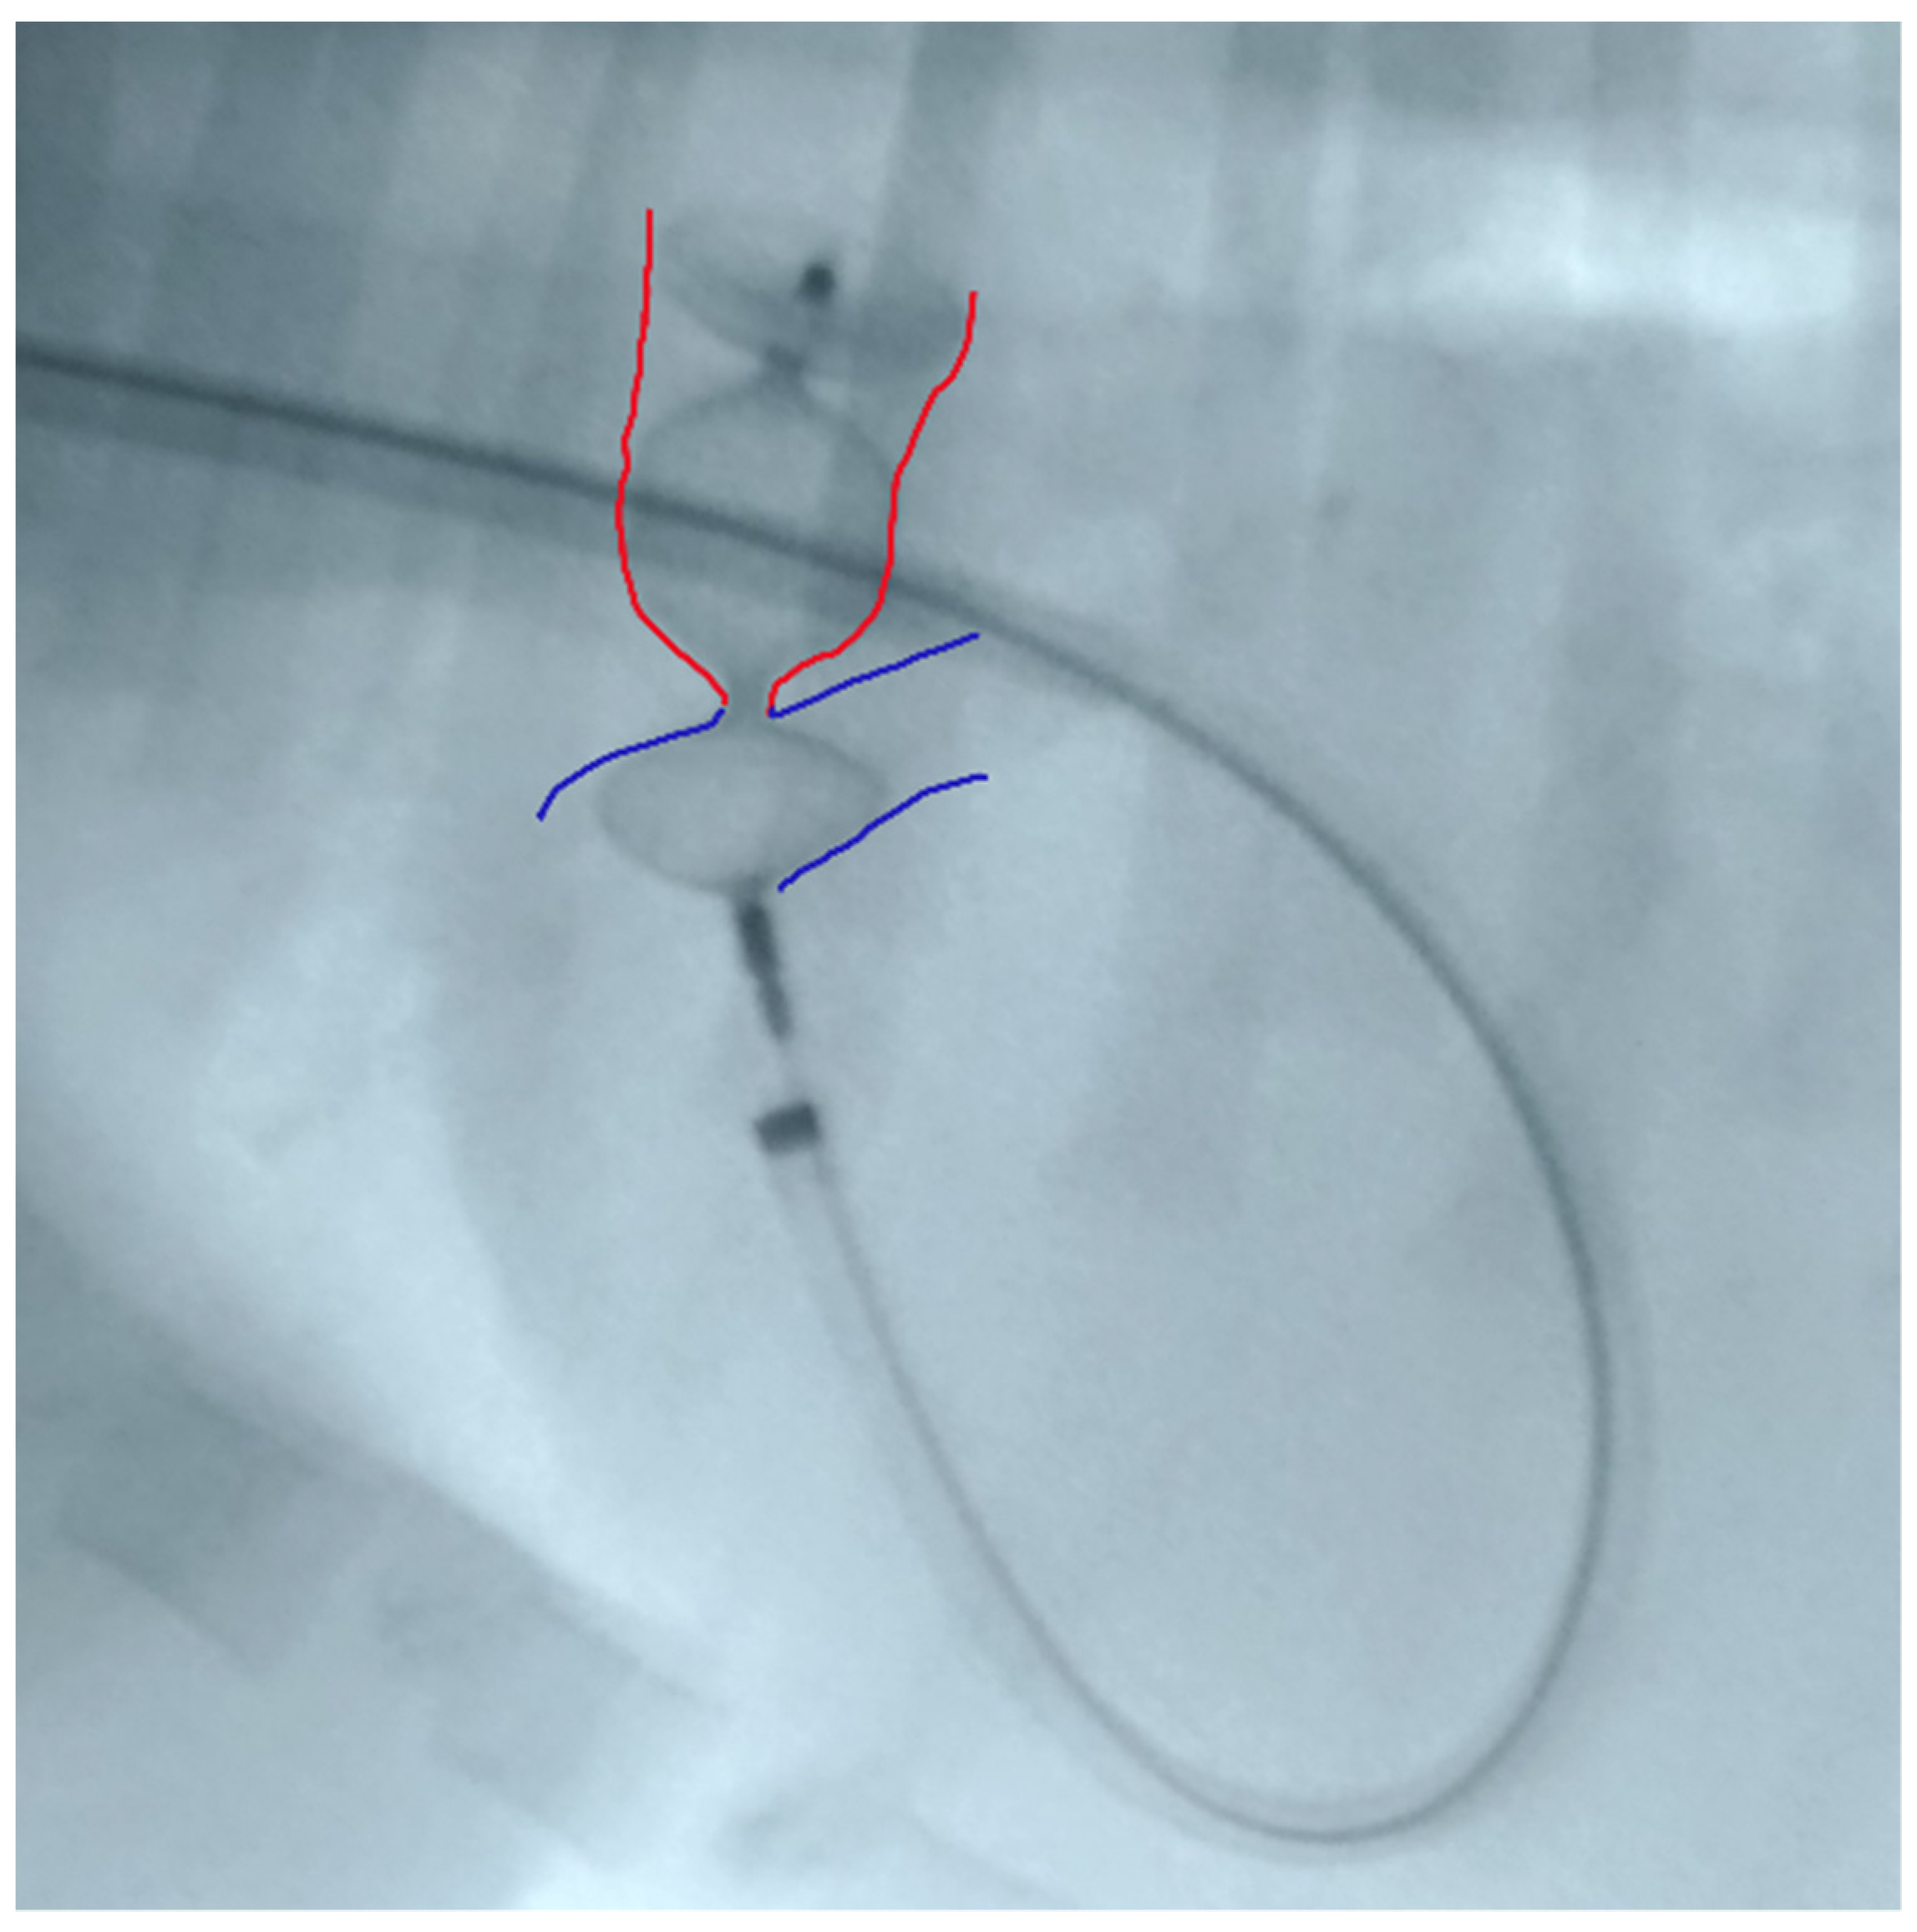

The device was introduced into the Balkin guiding sheath through the Check-Flo Valve and then advanced carefully until the distal disc was expanded into the descending aorta near the ductus. The partially-deployed AVP II, the attached delivery cable and the guiding sheath were gently pulled back simultaneously, until the distal disc engaged the aortic ostium of the PDA. The guiding sheath then was retracted while slightly pushing the delivery wire, allowing the central component of the device to expand into the PDA ampulla (Figure 3).

The proximal disk was then deployed in the main pulmonary artery with a firm but not excessive traction that was sufficient to create a slight distension of the proximal disc. This guarantees its position in the pulmonary artery, while the lack of waist in the device central component indicates that it is totally positioned in the ampulla and is not engaged in the ostium (Figure 4).

Figure 4. Device deployed in the main pulmonary artery with slight distension of the proximal disc. Red: ductal ampulla; Blue: pulmonary artery.